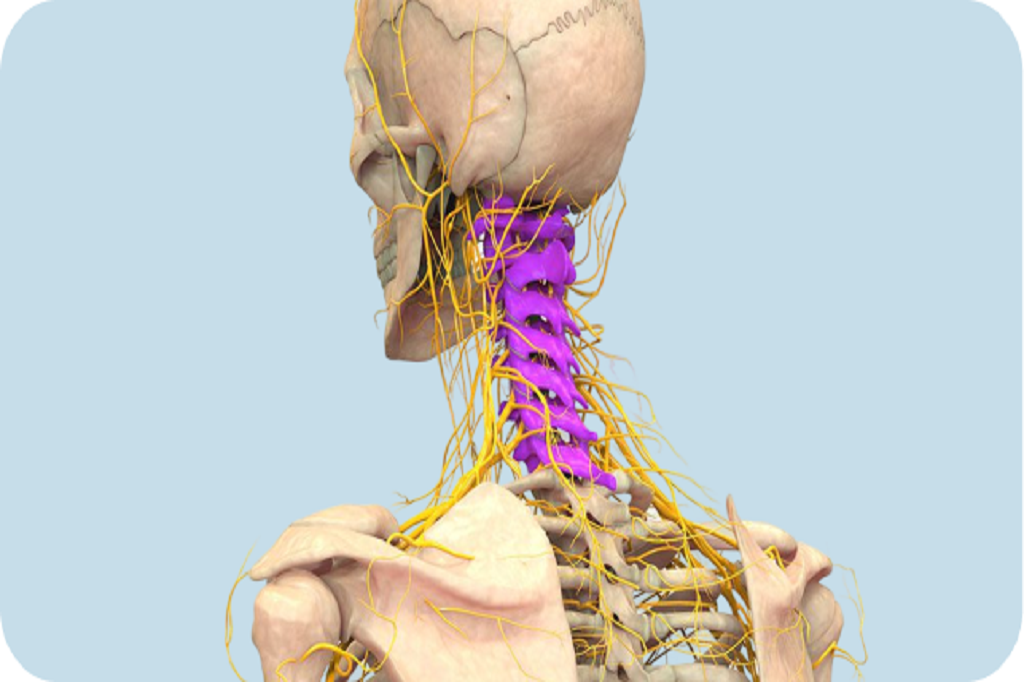

Neck pain is a common condition that can result from muscle strain, poor posture, arthritis, or compression of the nerves in the cervical spine. It may cause stiffness, headaches, or radiating pain into the shoulders and arms. For some, it becomes a chronic issue that affects work, sleep, and quality of life.

Spinal stenosis (narrowing of cervical spine canal)

At Armada Medical Center, Dr. Babak Babakhani, MD, PhD, provides advanced, minimally invasive treatments tailored to the cause of neck pain: